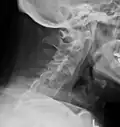

X-rays

The earliest changes demonstrable by plain X-ray shows erosions and sclerosis in sacroiliac joints. Progression of the erosions leads to widening of the joint space and bony sclerosis. X-ray spine can reveal squaring of vertebrae with bony spur formation called syndesmophyte. This causes the bamboo spine appearance. A drawback of X-ray diagnosis is the signs and symptoms of AS have usually been established as long as 7–10 years prior to X-ray-evident changes occurring on a plain film X-ray, which means a delay of as long as 10 years before adequate therapies can be introduced.[25]

Options for earlier diagnosis are tomography and MRI of the sacroiliac joints, but the reliability of these tests is still unclear.

Lateral X-ray of the mid back in ankylosing spondylitis -

Lateral X-ray of the neck in ankylosing spondylitis -